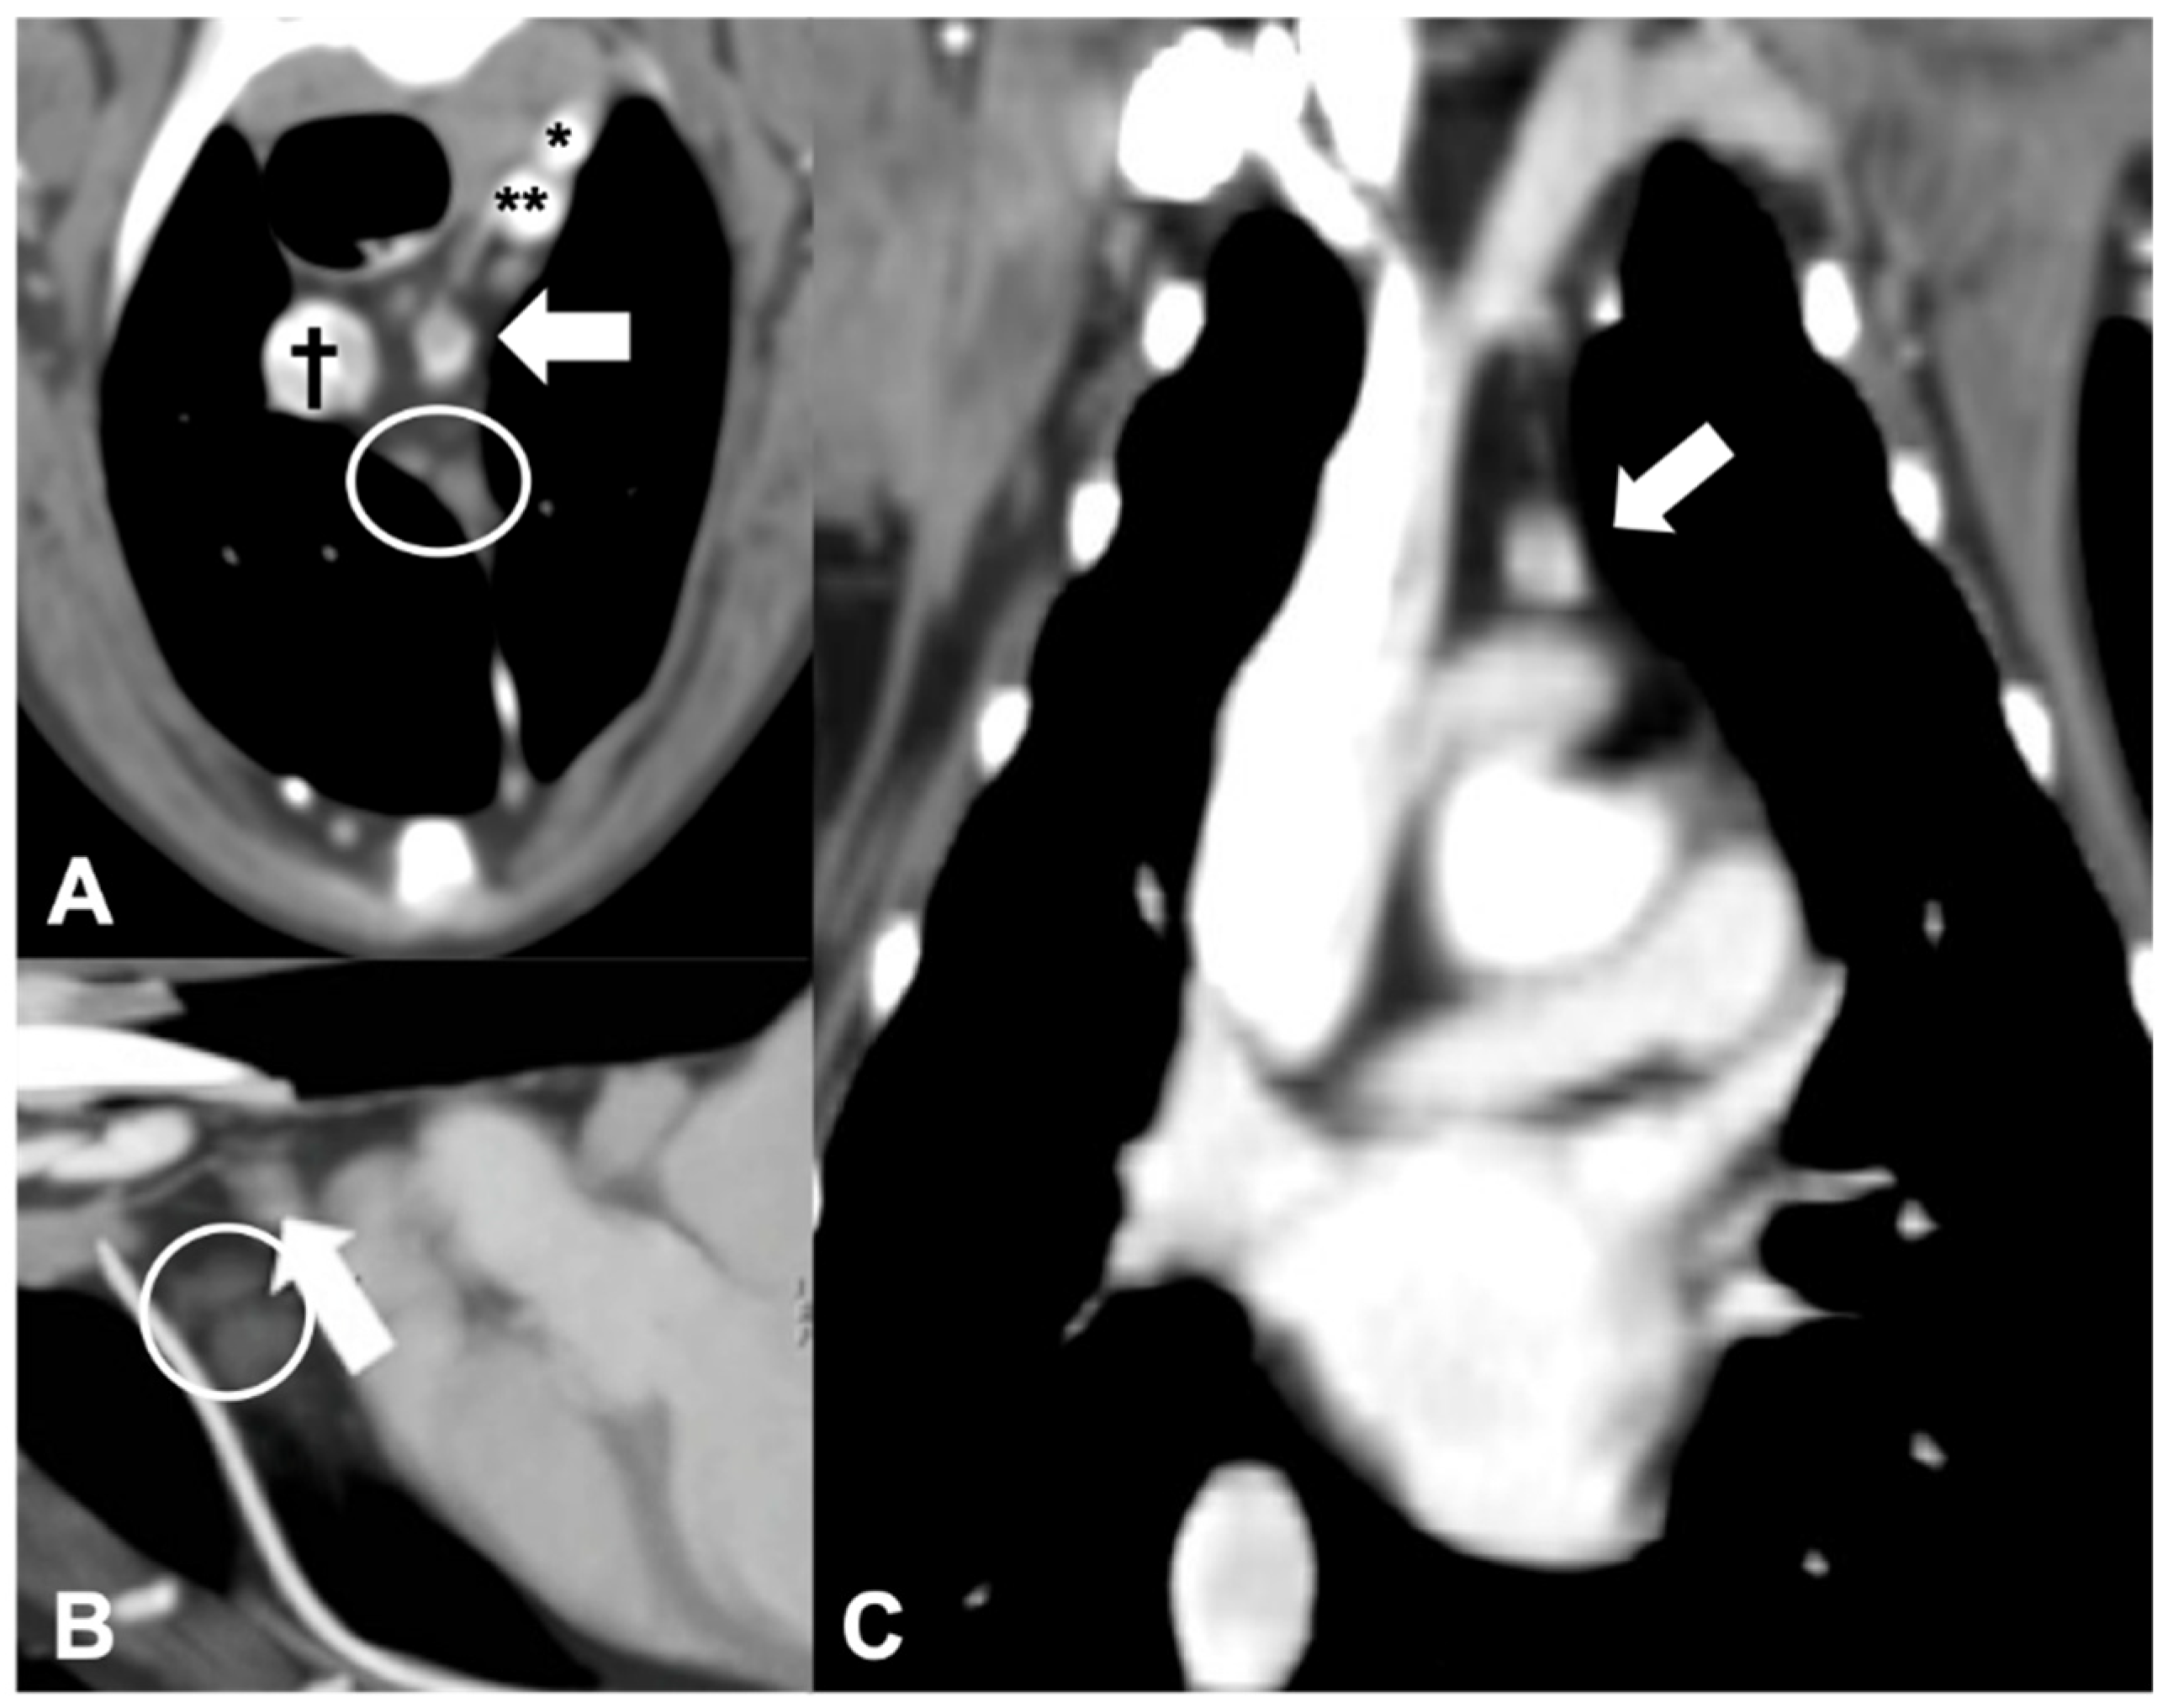

Only 1 of the 21 dogs included presented with primary hyperparathyroidism caused by an ectopic parathyroid adenocarcinoma. The nodule in this case was located in the cranial mediastinum, between the cranial mediastinal lymph nodes and the brachiocephalic trunk, rounded, and with heterogeneous contrast enhancement (Figure 5). Despite the localization, the presence of a single abnormal cranial mediastinal lymph node was considered unlikely and the presumptive diagnosis of ectopic parathyroid tissue was made based on the CT (than confirmed by histological examination).

Figure 5.

CT appearance of an ectopic parathyroid gland adenocarcinoma. Post-contrast transverse (A), sagittal (B), and dorsal (C) CT reconstruction images of a dog with diagnosed parathyroid gland adenocarcinoma (arrow) at the level of the cranial mediastinum. † = cranial vena cava; * = left subclavian artery; ** = brachiocephalic trunk. Note the cranial mediastinal lymph nodes (within the circle).